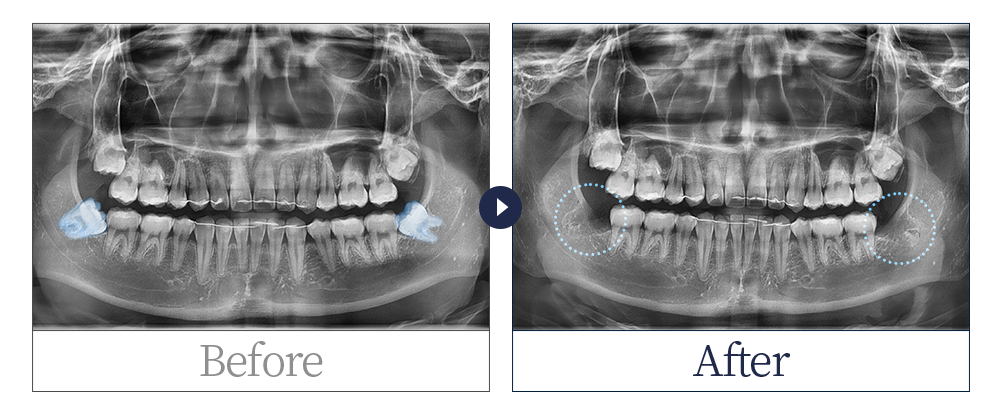

제목 20대 남 사랑니 발치 카테고리 사랑니발치

20대 남 완전 매복 사랑니 발치 사례입니다.

치료 전: 20221022

치료 후: 20221119